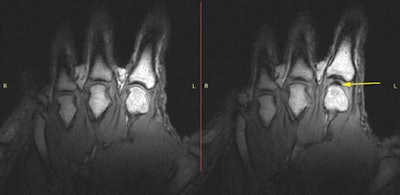

Kawchuk's group used a Magnetom Sonata (Siemens Healthcare) 1.5-tesla MRI system with a finger coil provided by the company. For the study, the single participant lay prone with his hand attached to the radiofrequency coil, which was then threaded through the magnet. The team took static images of the subject's 10 metacarpophalangeal (MCP) joints before and after taking a cine MR acquisition, during which force was increasingly applied manually through the coil until the study participant indicated that the joint had cracked (PLOS One, April 15, 2015).

radiofrequency coil (above left). The participant's hand within the imaging magnet (above right). All images courtesy of PLOS One.

All 10 of the subject's MCP joints cracked. The static MR images showed normal MCP joints without any gas bubbles before cracking; after cracking, static imaging showed a dark intra-articular space, according to Kawchuk's team.

A surprising finding was that the researchers observed a white flash just before the joint cracked, Kawchuk said.

"The white signal we saw in the joint just before it cracked was likely caused by fluid collecting between the joint surfaces as tension increased," he said. "We'd like to explore if this is a sign of cartilage health, which could offer a noninvasive way of determining a patient's joint status."